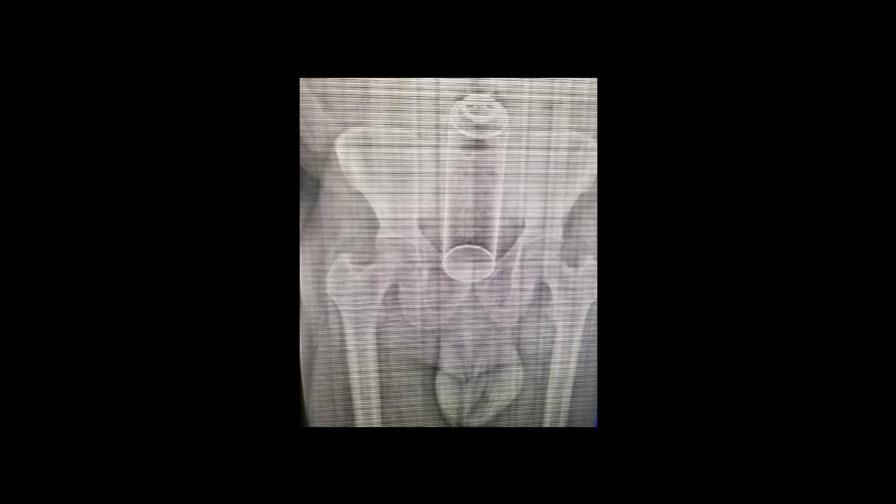

El señor de 40 años, que llegó al hospital Francisco Moscoso Puello con un frasco de metal alojado en el tracto intestinal, se encuentra estable, fuera de observación.

El paciente tuvo que ser sometido quirúrgicamente para retirar un frasco, luego de sostener relaciones sexuales con su esposa, quien le introdujo el objeto.

El director del Servicio Nacional de Salud (SNS) informó que un médico residente de anestesiología es uno de los responsables de difundir, a través de las redes sociales, la imagen de una radiografía realizada al paciente y que luego fue publicada en los medios de comunicación.

Ante las críticas de confidencialidad de los pacientes, expresó que el personal que divulgó las fotos violó el juramento hipocrático del médico que establece la discreción en el ejercicio de su profesión y también la Ley General de Salud que dispone la confidencialidad del expediente clínico.